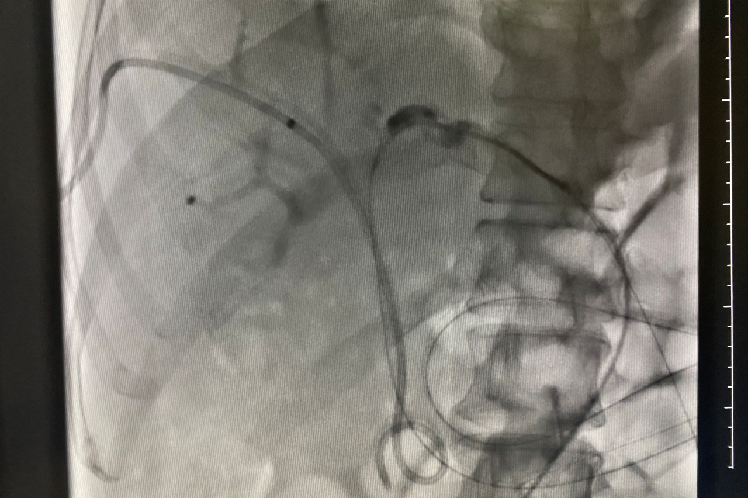

术后4天复查:左胆管造影剂通过原狭窄段良好,顺利流入十二指肠,给予拔除

术后4天复查:右肝部分胆管造影剂排除迟缓,保留右侧胆道引流管,继续外引流,择期复查